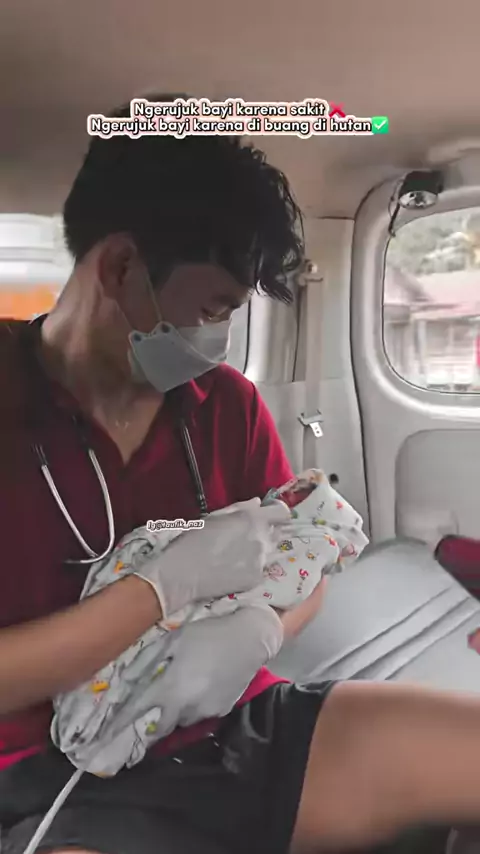

Maaf yah dek kk ga bisa nolongin mama kamu 😭#eklamsi #hipertensi #hdk #hipertensidalamkehamilan #kejang #eclamsia #mom #serunyabelajar